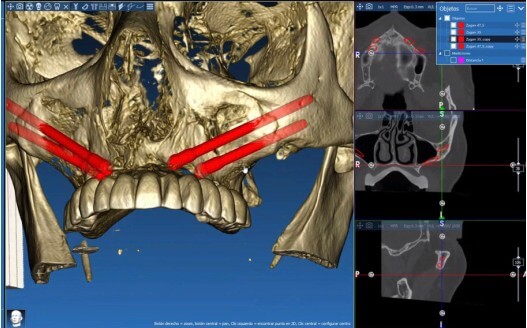

Realizamos CT helicoidal y con FOV ampliado, imprescindible para el diseño de las guías.

Planificamos cuidadosamente la colocación de los implantes teniendo en cuenta, tanto la anatomía maxilofacial como la de la futura prótesis

Planificación 3D personalizada

Se planifica rehabilitación completa con 4 implantes Zygoma.

Planificación 3D y confección de férulas quirúrgicas para abordaje guiado.